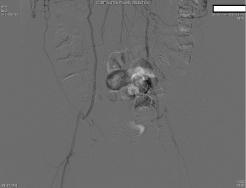

Preoperatively, the surgery service was queried by the anesthesiologist as to whether the routes of collateralization to the lower extremities were known. The response indicated that there had been intraabdominal collaterals demonstrated on angiography from the radial artery catheterization upon admission. The patient was then transported to the operating room, and a radial arterial line was placed during preoxygenation and prior to induction. After further consideration, the surgeon requested a delay of induction of anesthesia for further angiography review. Upon examination, a large right inferior epigastric artery was noted on the preoperative catheterization films, suggesting that collateral blood from the right internal mammary artery may supply the right lower extremity. The origin of collateral flow, however, could not be determined. Existing angiography was also unable to clearly demonstrate the collateral blood flow to the left lower extremity. At this point, the case was aborted before induction of anesthesia, and further angiography studies were ordered in consultation with a vascular surgeon. A subsequent aortogram and angiography of the internal mammary arteries demonstrated that collateral flow to the lower extremities was dependent on both the left and right internal mammary arteries (Figure 1, Figure 2 and Figure 3). Gastroepiploic artery was not considered as an alternative to the LIMA because of lack of institutional experience with the procedure.

Figure 2: Angiogram demonstrating collateral flow to the lower extremities from the internal mammary arteries via the inferior epigastric arteries.